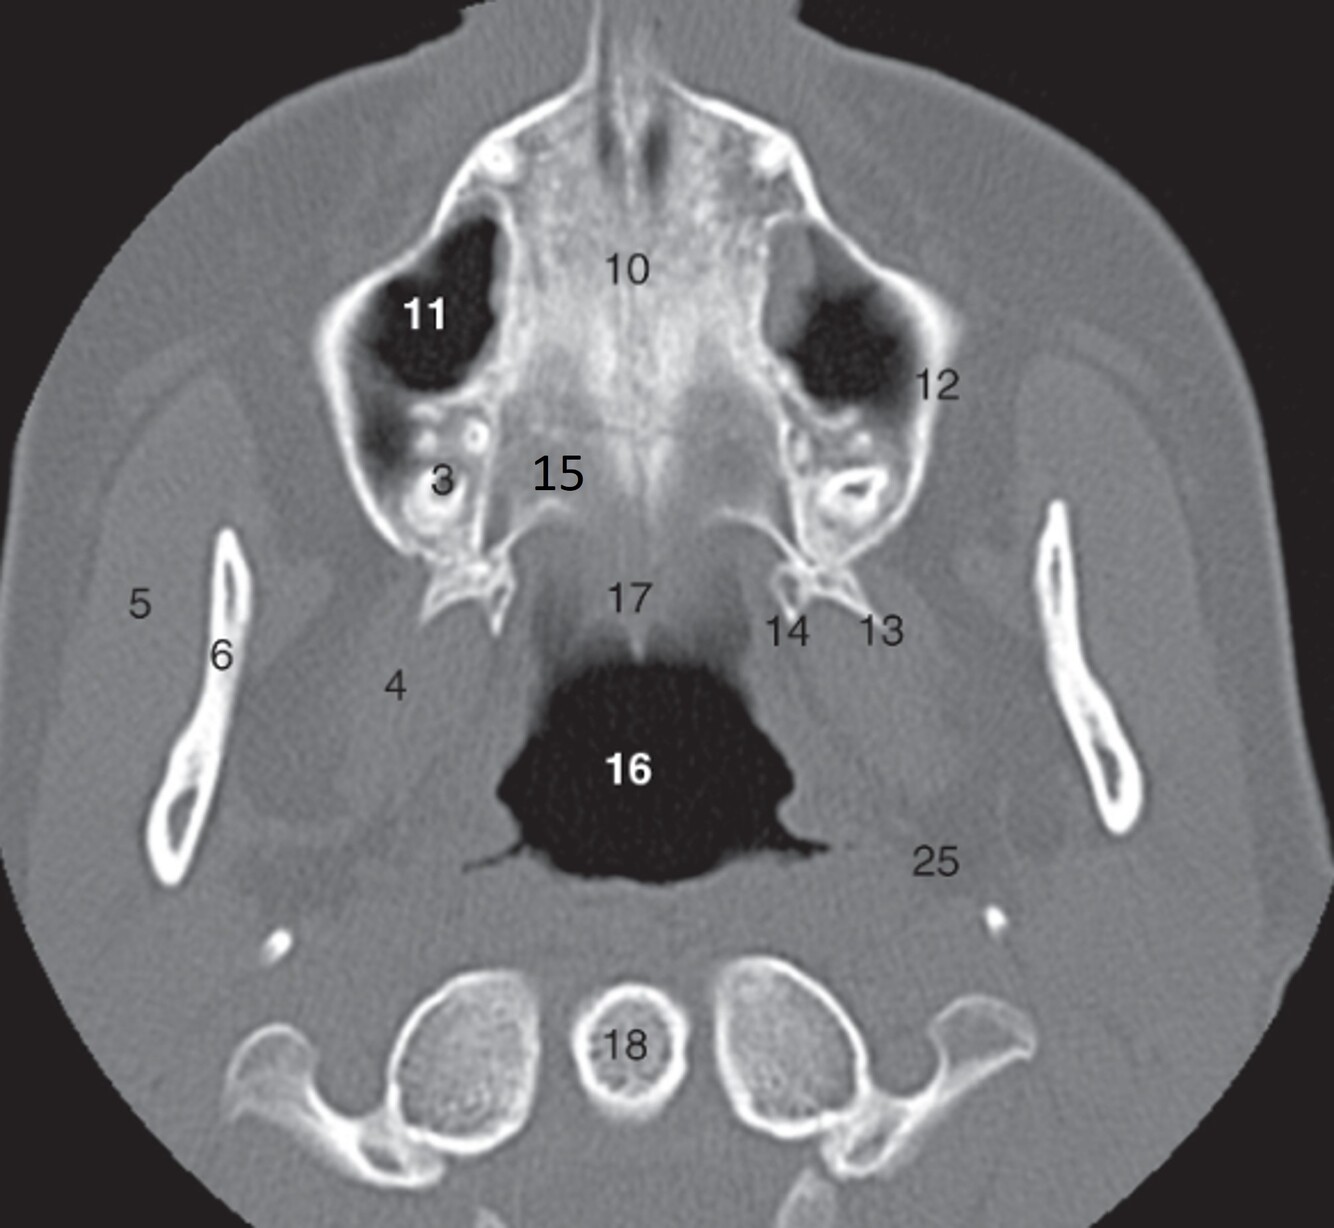

1

Label 5,6,10,11,12

A

5-Rt masseter muscle

6-Rt ramus of mandible

10=Median suture (hard palate)

11=Rt maxillary sinus

12=Rt Maxilla

2

Label 13-18

13=Lt lateral pterygoid process (Sphenoid)

14=Lt. medial pterygoid process (Sphenoid)

15=Horizontal plate (Rt palatine)

16=Nasopharynx

18=Odontoid process of C2